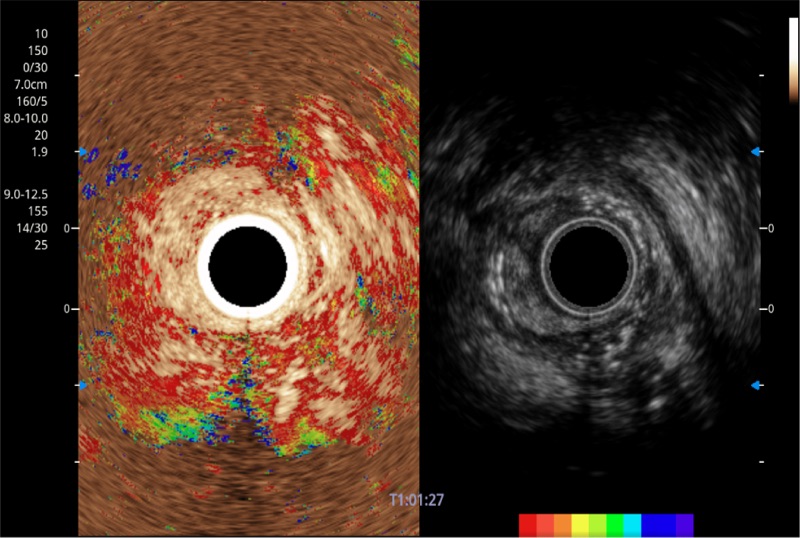

TIC时间强度分析曲线

具有四种造影成像效果